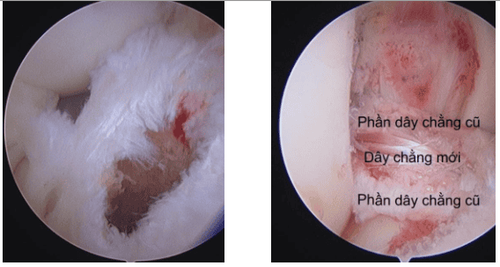

Phẫu thuật viên mổ dây chằng chéo trước sẽ có những lúc đặt không đúng vị trí tối ưu, thậm chí là đặt ra ngoài. Theo một nghiên cứu thì có thể có đến 36% các trường hợp sẽ bị đặt đường hầm đùi không đúng vùng tối ưu, tức cứ 10 trường hợp thì có thể có 3-4 trường hợp không đạt vị trí tốt nhất. Và với việc có sự hỗ trợ của công nghệ 3D thì việc đặt chính xác vị trí dây chằng mới là 100%. Bạn có thể hình dung trong trường hợp của cung thủ, nếu có bắn không chính xác thì có thể đến tận bia bắn, nhổ mũi tên bắn sai và cắm lại vào hồng tâm vậy. Hai hình ảnh dưới đây minh họa cho cái bia bắn tưởng tượng trên người bệnh.

Ngoài ra, công nghệ 3D với sự hỗ trợ của Robot còn giúp phẫu thuật viên chỉ cần can thiệp tối thiểu, bảo tồn tối đa phần di tích còn lại của dây chằng cũ mà vẫn cho phép đặt chính xác vị trí dây chằng mới. Kết hợp với các phương pháp và phương tiện tốt hiện nay, người bệnh đứt dây chằng chéo trước hoàn toàn có thể tự tin phẫu thuật và phục hồi một cách chuyên nghiệp để sớm quay lại với đam mê của mình.